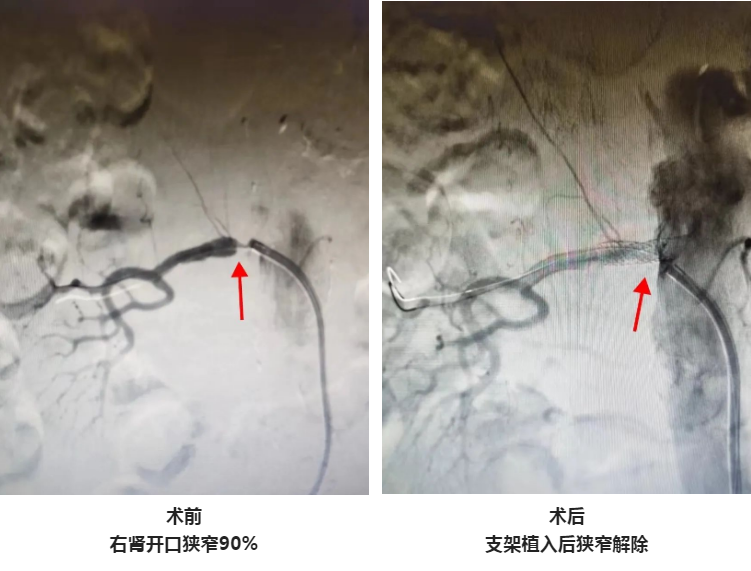

家住星城的李奶奶因高血压、血压忽高忽低入住北京燕化医院星城院区心血管内科,经检查后发现,患者并不是传统意义上的原发性高血压,而是肾动脉重度狭窄引起的继发性高血压,行肾动脉造影发现,患者右侧肾动脉重度狭窄,虽然没有出现肾脏萎缩,但已经出现肾功能受损,在药物治疗的同时,最好的治疗方法是植入肾动脉支架。

王志勇副主任医师及星城介入团队全面评估患者病情,并和患者家属充分沟通后,成功为患者实施了肾动脉支架植入术,在患者右肾动脉开口植入一枚支架以缓解肾动脉狭窄的情况,整个手术过程不到1个小时,术后患者恢复良好,血压控制良好。